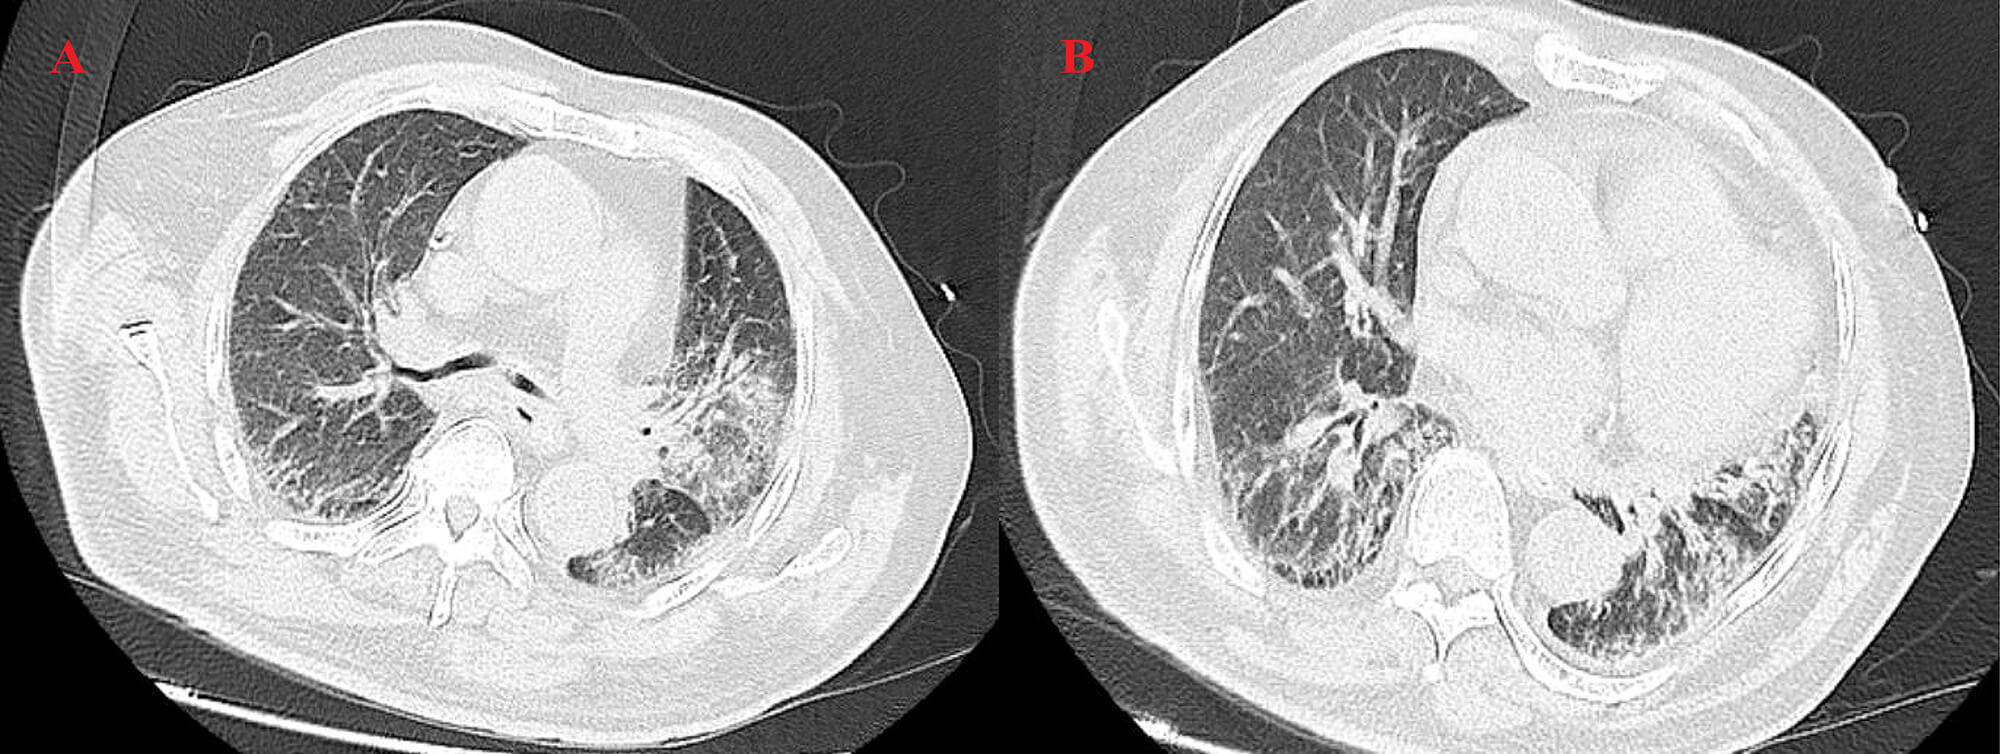

In July 2024, the patient presented to the Department of Neurology at the Second Affiliated Hospital, Zhejiang University School of Medicine with limb weakness but did not receive specific treatment at that time. A high-resolution computed tomography (HRCT) scan of the chest without contrast (Fig. 1) revealed a mass lesion in the left upper lobe and patchy consolidation in the right lower lobe. Bronchoscopic biopsy showed atypical naked nuclei in the mediastinal 4R lymph node and the anterior segment of the right upper lobe, consistent with small cell carcinoma. Immunohistochemistry (IHC) demonstrated positivity for pan-cytokeratin (CK-PAN), thyroid transcription factor-1 (TTF-1), synaptophysin, chromogranin A, cluster of differentiation (CD) 56, and insulinoma-associated protein 1 (INSM1), with a Kiel-67 (Ki-67) index of approximately 60%, confirming the diagnosis of SCLC (Fig. 2) [12]. Cytological examination of the 4R lymph node also revealed small cell carcinoma cells. Electromyography performed on 5 August 2024, demonstrated a low-frequency decrement and high-frequency increment across multiple muscles; reduced amplitudes and absent responses in motor and sensory nerves of the right lower limb; and neurogenic changes in several examined muscles (Table 1). The patient received 2 cycles of etoposide plus carboplatin (EC), followed by 4 cycles of EC combined with durvalumab, and subsequently 3 cycles of durvalumab maintenance therapy, after which muscle strength improved.

Fig. 1.

Baseline chest high-resolution computed tomography (HRCT) findings. HRCT of the chest without contrast performed on 6 July 2024 showed a mass lesion in the left upper lobe (A) and patchy consolidation in the right lower lobe (B).